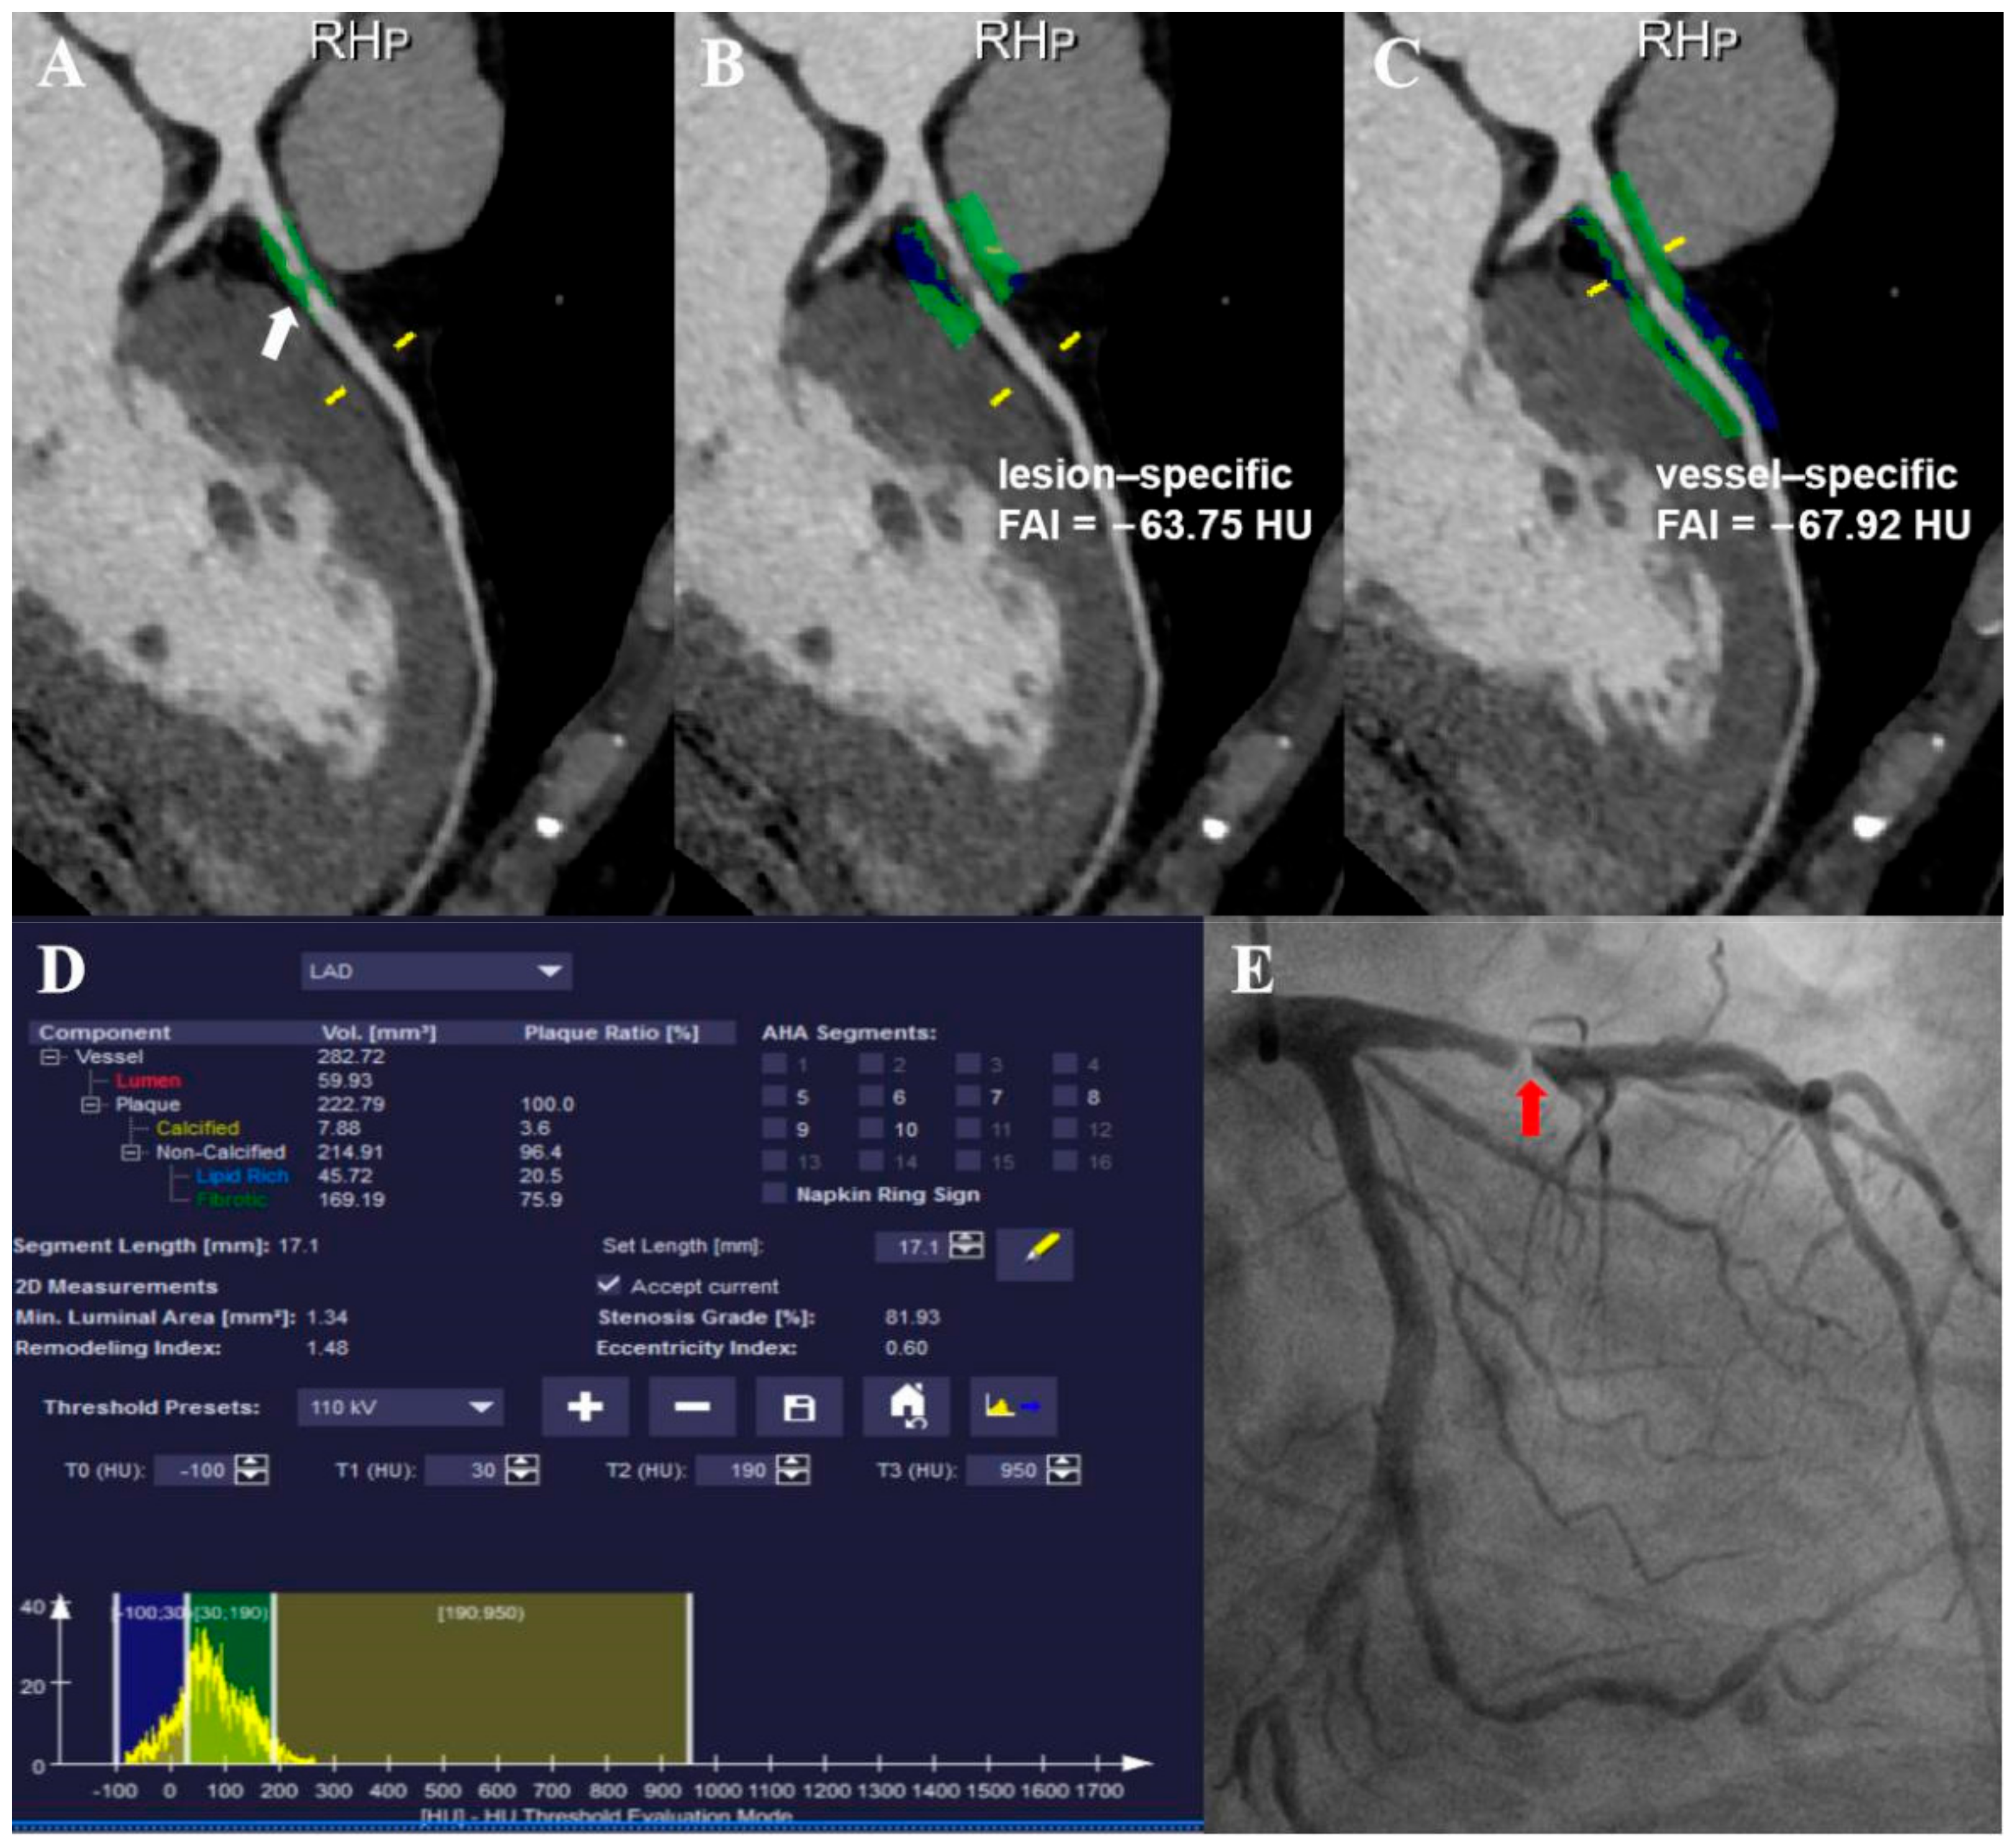

2.4. Perivascular Fat Attenuation Index Acquisition

3.4. Relationship between Vessel-Specific FAI, Lesion-Specific FAI, and Coronary Stenosis